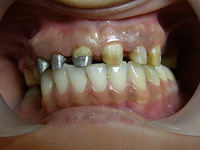

Situatie initiala

Proteza scheletata